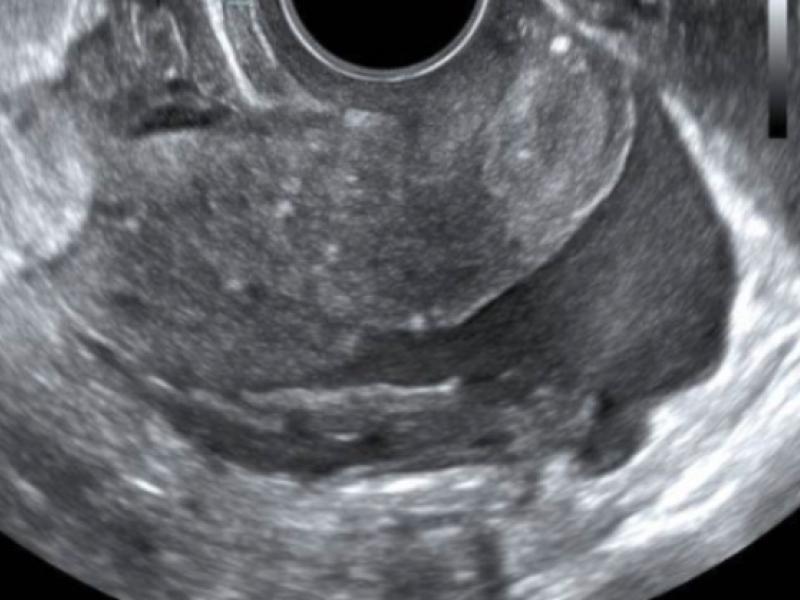

A 27 yo F presents to the ED with severe RLQ abdominal pain